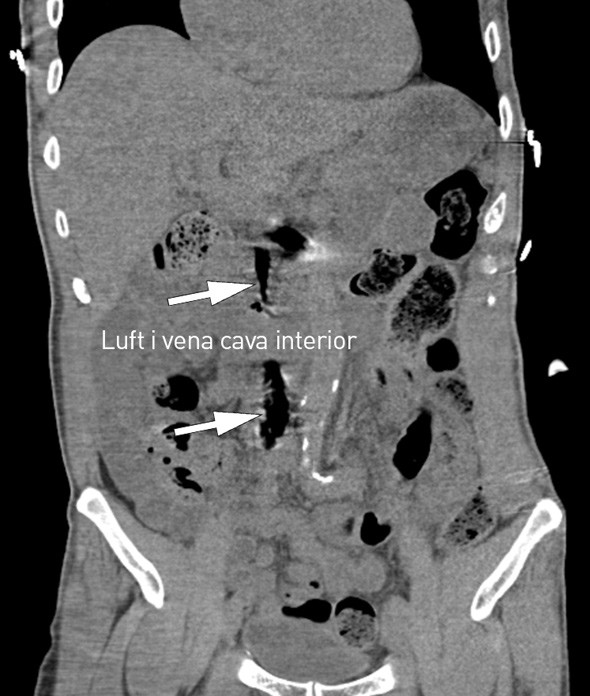

På sykehuset fikk han flere venekanyler i overekstremitetene. Den intraossøse nålen ble fjernet etter å ha vært åpen rundt en halvtime mens pasienten lå i sjokkleie. CT-undersøkelse av thorax, abdomen og bekken uten intravenøs kontrast tatt kort tid etter ankomst viste luft i høyre vena femoralis, vena cava inferior og venstre nyrevene. Sikker årsak til hjertestans ble ikke funnet, og pasienten døde etter et kort intensivopphold.